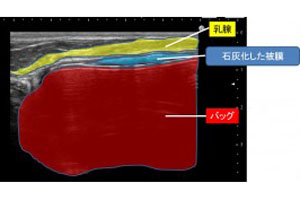

豊胸シリコンバッグの被膜は、エコー画像でも確認できる

豊胸シリコンバッグをバストに挿入すると、周囲に被膜が形成されます。この被膜は、体内に異物が入ってきた際の生体反応として形成されるものであり、これ自体は正常な反応です。ただ場合によっては、この被膜が石灰化して、固い卵の殻のような質感になってしまうことがあります。

被膜は、体内のカルシウム成分の影響で石灰化します。バッグを抜去・除去する際には、基本的には被膜の石灰化した部分だけを除去して、その他の部分はきれいに残します。

バストが凹んでえぐれたような胸になるため、豊胸シリコンバッグ抜去後はショックを受ける方が少なくありません。そのため、バッグ抜去後は安全な脂肪を注入して美しく蘇らせる道(脂肪注入法)がおすすめです。その際は、エコーで被膜の状態を確認しながら、石灰化を除去するなどして正しく処置をします。